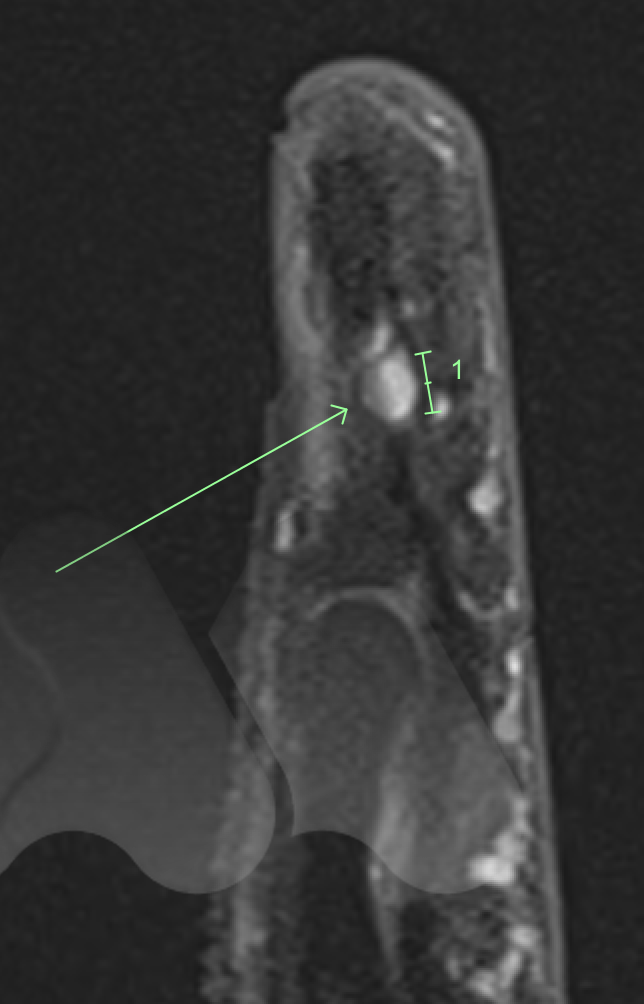

This is a rare benign (non-cancerous) growth often under the fingernail or fingertip pulp and can involve bone.

It commonly causes severe pain in the fingertip in cold environments and extreme pain and sensitivity to touch. X-Ray and MRI can be useful tests in confirming the diagnosis.